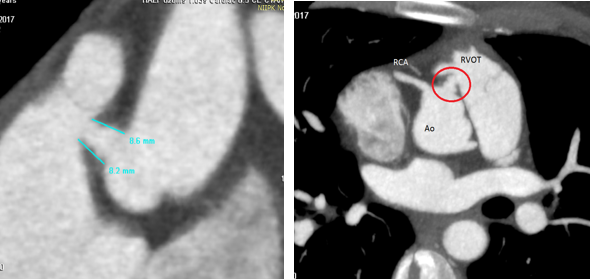

Выполнено МСКТ исследовании с контрастом: определяется дефект между правым коронарным синусом Вальсальвы и ПЖ в области ВОПЖ. Расстояние от края дефекта до устья правой коронарной артерии – около 3,0- 4,0 мм. Размеры фистулы со стороны правого желудочка - 4,5х 5,0 мм, со стороны синуса аорты - до 6,0х 6,0 мм, протяженность стенок (длина канала дефекта): справа и слева - около 9,0 и 6,0 мм соответственно. (Рис 2.)

Рисунок 2.